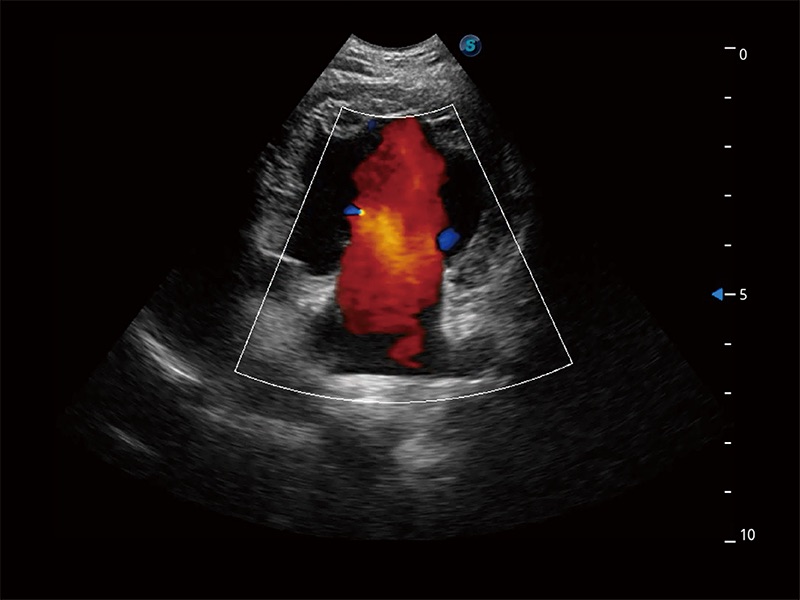

ProPet 80 配备了丰富的心脏探头群、先进的成像技术和专业的心脏测量工具,可帮助动物医生为不同体型和生理结构的动物提供心脏和心肌功能的全面评估。

实时用颜色表示心肌组织运动,观察和定量组织的运动情況,对快速检测与评估心肌的灌注和活性、电传导及心肌收缩和舒张功能等均能提供重要的诊断信息。